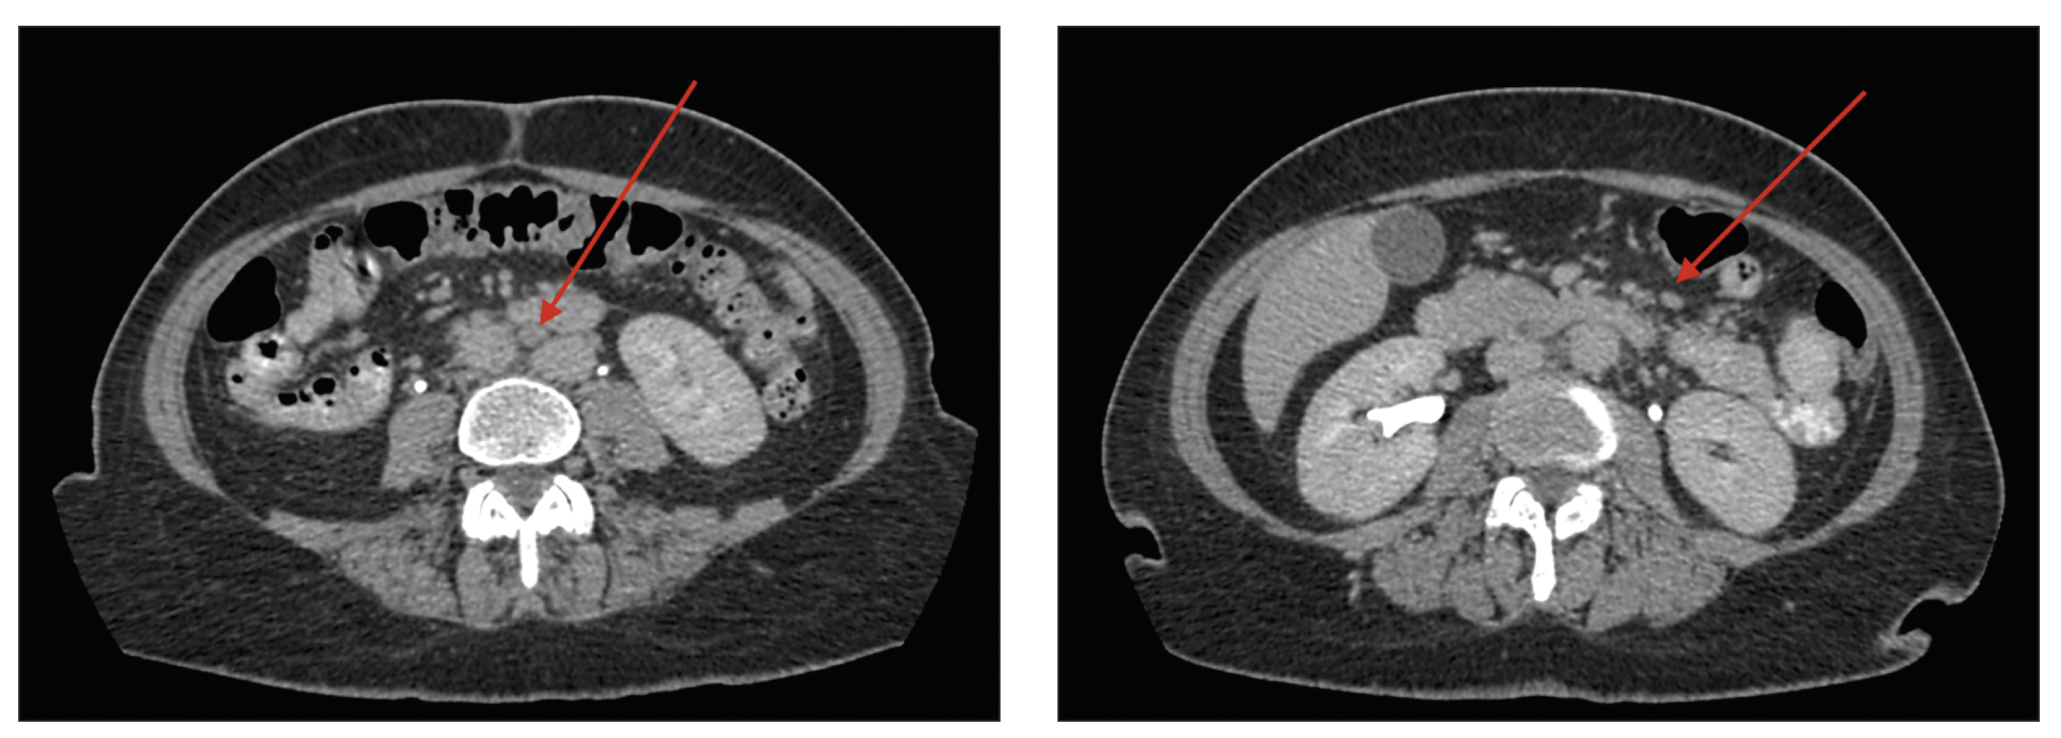

Upper gastrointestinal tract esophagogastroduodenoscopy revealed no abnormalities. A colonoscopy revealed erosive lesions of the descending colon, sigmoid, and rectum mucosa. The histology of the colon biopsy samples revealed catarrhal colitis. Abdominal CT with intravenous contrast (Figure 2) showed several abdominal lymph nodes (para-aortic and superior mesenteric lymph nodes, up to 10-mm short-axis diameter) during the patient’s stay in the Infection Department inpatient unit.

Fig. 2. Abdominal computed tomography scan with intravenous contrast (September 2020); axial plane: the red arrows show intraperitoneal lymph nodes.

The findings were classified as lymphadenopathy, and the patient was referred to a hematologist in September 2020. A bone marrow trephine sample was conducted, followed by histological examination; no indication of the hematopoietic system was identified. Compared with the earlier scan in August 2020 (see Figure 1), follow-up thoracic CT (Figure 3) revealed effusion resorption from the pleural cavities and partial regress of hypoventilatory changes in the basal parts of the lungs. Otherwise, no significant changes were found.

Fig. 3. Thoracic computed tomography scans (September 2020); axial plane: the red arrows show (a) the area with partial regression of the hypoventilation changes and (b) lack of pleural effusion.